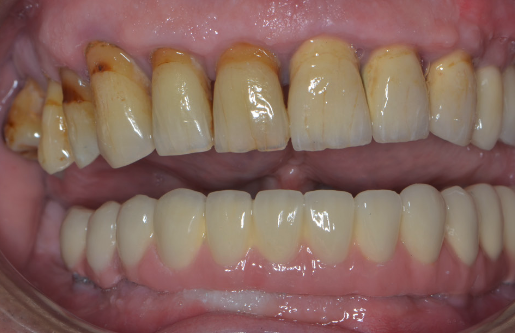

Lucrările pot fi realizate, în funcție de caz, pe ambele maxilare sau doar pe unul dintre maxilare. Atunci când pacientul prezintă lucrări vechi necorespunzătoare, sprijinite pe dinți care prezintă mobilitate crescută, (Fig. 3.6.1 lucrarea anterioară, mandibulară și Fig. 3.6.2) pacientul va rămâne edentat (fără dinți) în urma extracțiilor dinților mobili. În cazul acestui pacient, toți dinții superiori prezintă rectracții ale gingiei, iar cei din partea stângă (incisivul central, incisivul lateral și caninul) au fost tratați endodontic (tratamente de canal). Acest lucru a indicat acoperirea lor cu coroane metalo-ceramice (Fig. 3.6.3).